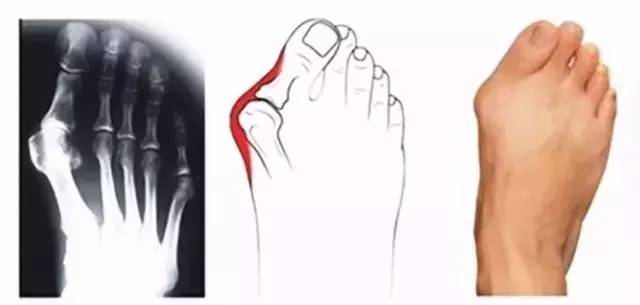

“拇趾外翻”,是引起足部不适的最常见疾病之一,俗称大脚骨,主要表现为脚部畸形和疼痛:大脚趾向外翻,向其它脚趾方向偏斜,同时伴有脚拇趾根部的跖骨头明显突出(畸形严重时,趾骨头突出处可呈半球形),第二脚趾也可因为挤压而向脚背面突出,如下图所示:

拇外翻